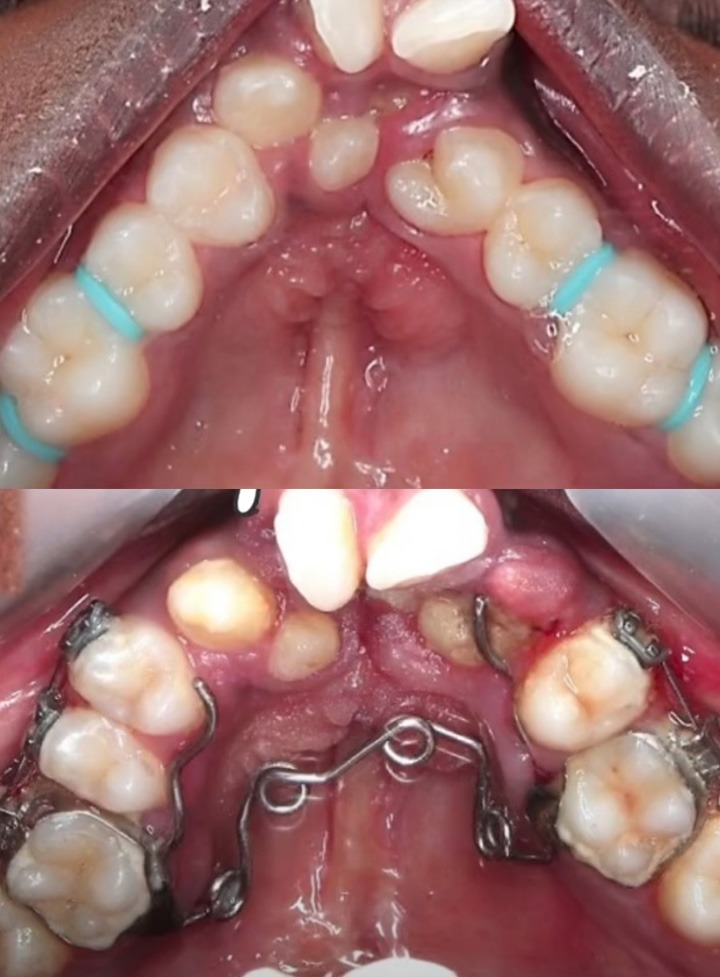

Rapid Maxillary Expansion for Narrow Arch

Rapid maxillary expansion (RME) is a highly effective treatment offered at Richardson Face Hospital, recognized for providing the best orthodontics treatment in Bangalore. This procedure is ideal for patients with a narrow upper jaw, helping to create more space for teeth alignment and improving overall bite function.

The process begins with a comprehensive evaluation, followed by the fitting of a custom-made expander. The device, typically attached to the upper molars, is gradually adjusted to apply gentle pressure, widening the upper jaw over time. At Richardson Face Hospital, we specialize in the best orthodontics treatment in Bangalore, using advanced techniques like rapid maxillary expansion (RME) to improve bite function and create more space for proper teeth alignment. Regular check-ups ensure the expansion progresses correctly for effective results.

Regular check-ups are essential to monitor the progress of the expansion and make any necessary adjustments. RME is particularly beneficial for children and adolescents, as their bones are still growing and respond more effectively to orthodontic treatment. If you’re looking for the best orthodontics treatment in Bangalore, RME at Richardson Face Hospital offers a proven solution for enhanced dental health and improved smiles.